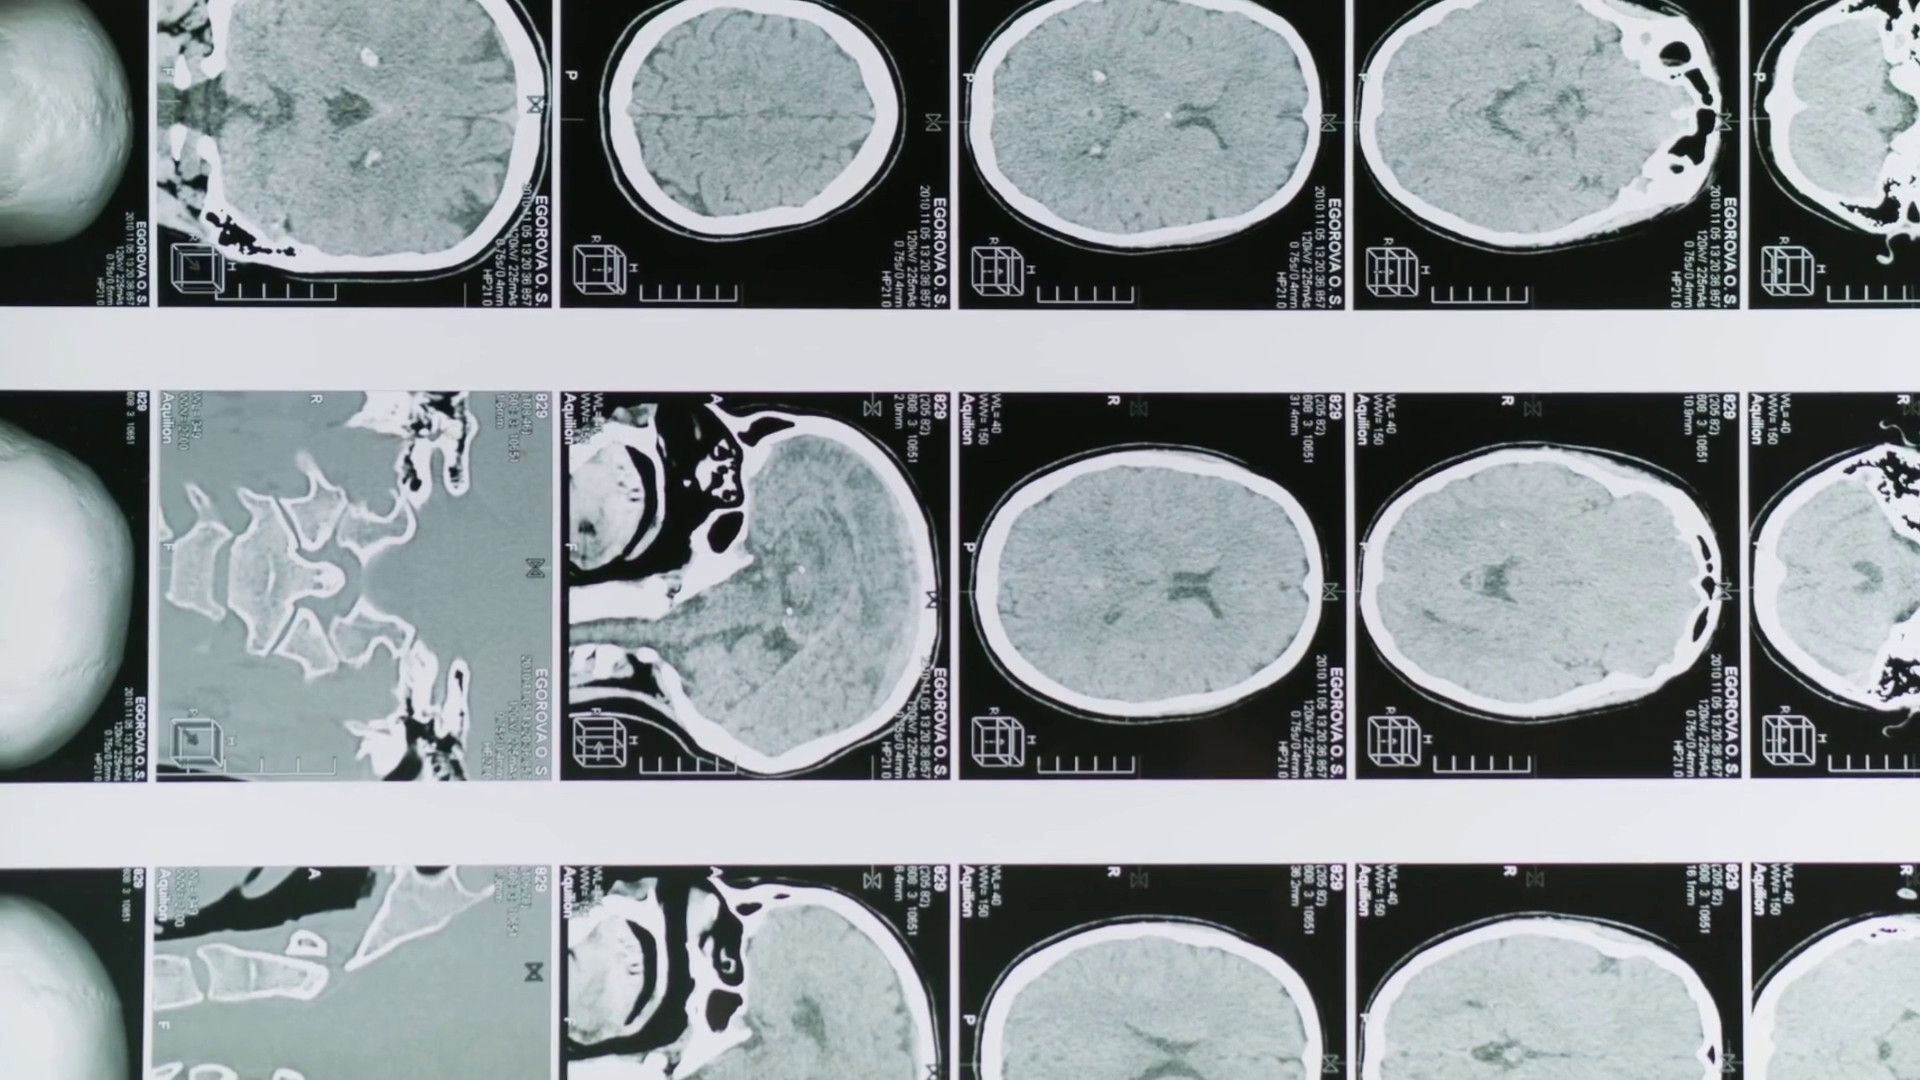

ROMA (ITALPRESS) – Una sperimentazione condotta per la prima volta su un campione di pazienti umani ha rivelato che la combinazione di curcumina e polidatina – due molecole naturali – migliora l’efficacia della terapia chemioterapica nel trattamento del glioblastoma, un tumore cerebrale particolarmente aggressivo. Il test è stato condotto da ricercatori dell’Istituto di farmacologia traslazionale del Consiglio nazionale delle ricerche e della Fondazione per la ricerca di terapie oncologiche integrate, e con la consulenza epidemiologica del Policlinico Gemelli. sat/gtr/col